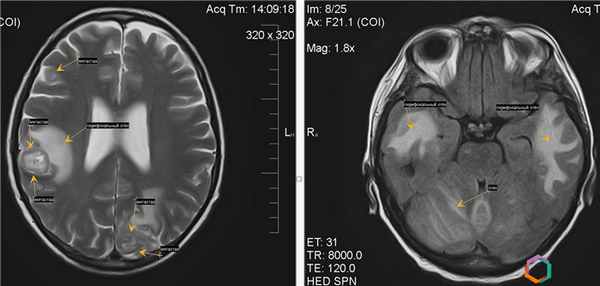

Рис. 4 Метастазы немелкоклеточного рака легкого в головной мозг до СРХГН и через 1 год после СРХГН

Рис. 5 Метастазы немелкоклеточного рака легкого в головной мозг до СРХГН и через 1 год после СРХГН